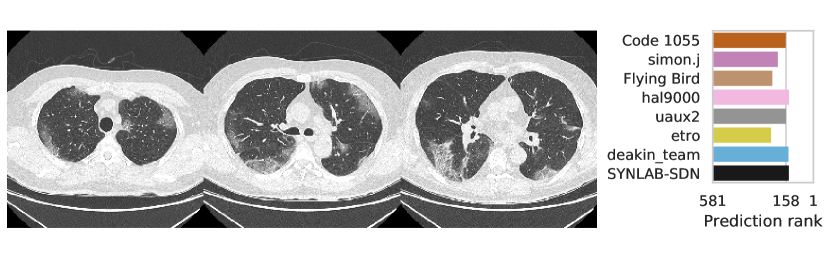

3.2.3 Performance

Table 1 shows the AUC on test set B for COVID-19 presence and severity of the teams that submitted to the Final phase. Figure 4 shows Receiving Operating Characteristics (ROC) curves of the six successful Final phase submissions for discriminating between severe and non-severe COVID-19 subjects from test set B. Figures 5 and 6 show how the finalists ranked the subjects from test set B with severe and non-severe COVID-19 respectively for presence of severe COVID-19. Figures 7 and 8 highlight some individual cases from test set B. During the original STOIC project [67], a logistic regression model was developed to predict severe COVID-19 using clinical variables and CT annotations by radiologists. It was developed and evaluated using the patients from the STOIC who were COVID-19 positive for both RT-PCR and CT, and had unenhanced CT. Of these 4238 patients, 1000 developed severe COVID-19. Revel and colleagues 6 reported an AUC for this model of 0.69 (CI: 0.67-0.71). To compare this model against the results from STOIC2021, an ensemble of the top three solutions for severe COVID-19 prediction was evaluated on the 367 patients from test set B who were COVID-19 positive for both RT-PCR and CT, and had unenhanced CT. 97 of these patients developed severe COVID-19. The top three ensemble achieved an AUC of 0.783 (CI: 0.706-0.848).